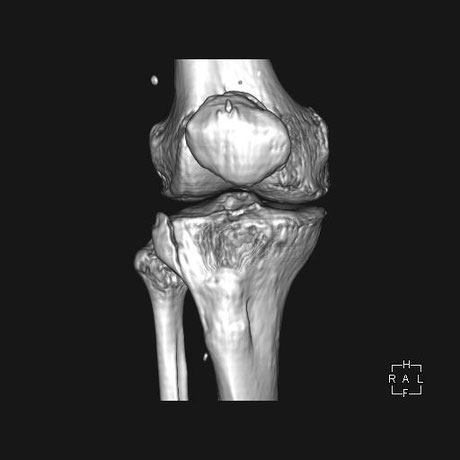

○ 脛骨高原骨折(プラトー骨折)

足を強く地面についた際に体の重みと下から突き上げる力により膝の関節周囲に骨折を起こします。

ちょうど土手が崩れるように折れています。通常は手術によりボルト打ち込み固定しますが、運よく関節面が維持されているので保存的(手術をしない)に治療することができました。

当初は関節内の骨折のため腫れがつよく安静処置が必要です。膝を包むような副子を作り包帯で固定。毎日当院の送迎により来院してもらい、湿布の交換、骨折部位の超音波治療、医療マッサージを施し現在も治療中。